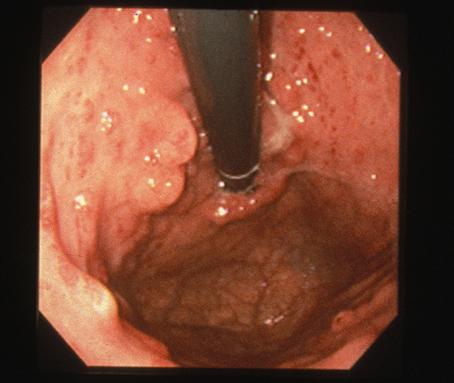

A case of gastric juvenile polyposis with multiple cancers.

Tokyo Pref., Cooperative study between National Cancer Center and Kyushu Cancer Center

Tumor-like lesions/Juvenile polyposis

Stomach/Body

Endoscopy